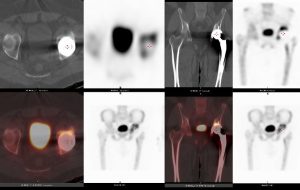

Scintigraphie osseuse : hyperhémie et hyperfixation à l’interface os-prothèse sur la pièce cotyloidienne en faveur d’un descellement mécanique. Pas d’anomalie sur la pièce fémorale.

TDM : Absence de liseré d’ostéolyse péri-prothétique sur les pièces cotyloidiennes et fémorale.Rétroversion de la pièce cotyloïdienne de 5°.Amyotrophie majeure avec involution graisseuse du psoas gauche.

Reprise chirurgicale : confirmation du descellement cotyloïdien avec micro-mouvements.Lésions de tendinopathies sur le psoas.Remplacement de la pièce cotyloidienne et excision des lésions de tendinopathies.

Descellement mécanique cotyloïdien d’une PTH et conflit avec le psoas